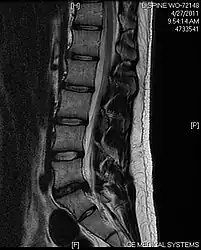

- Magnetic resonance imaging is the gold standard study for confirming a suspected LDH. With a diagnostic accuracy of 97%, it is the most sensitive study to visualize a herniated disc due to its significant ability in soft tissue visualization. MRI also has higher inter-observer reliability than other imaging modalities. It suggests disc herniation when it shows an increased T2-weighted signal at the posterior 10% of the disc. Degenerative disc diseases have shown a correlation with Modic type 1 changes. When evaluating for postoperative lumbar radiculopathies, the recommendation is that the MRI is performed with contrast unless otherwise contraindicated. MRI is more effective than CT in distinguishing inflammatory, malignant, or inflammatory etiologies of LDH. It is indicated relatively early in the course of evaluation (<8 weeks) when the patient presents with relative indications like significant pain, neurological motor deficits, and cauda equina syndrome. Diffusion tensor imaging is a type of MRI sequence used for detecting microstructural changes in the nerve root. It may be beneficial in understanding the changes that occur after herniated lumbar disc compresses a nerve root, and might help in differentiating the patients that need surgical intervention. In patients with a high suspicion of radiculopathy due to lumbar disc herniation, yet the MRI is equivocal or negative, nerve conduction studies are indicated.[46] T2-weighted images allow for clear visualization of protruded disc material in the spinal canal.

MRI scan of large herniation (on the right) of the disc between L4 and L5 vertebrae

A rather severe herniation of the L4–L5 disc

Example of a herniated disc at L5–S1 in the lumbar spine